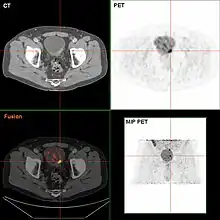

Bladder wall thickening due to cancer

Bladder tumor in FDG PET due to the high physiological FDG-concentration in the bladder, furosemide was supplied together with 200 MBq FDG. The uptake cranial to the lesion is a physiological uptake in the colon.